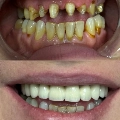

Ο Αλεβίζος Άκης είναι Χειρουργός Οδοντίατρος, Εμφυτευματολόγος και διατηρεί ιδιωτικό οδοντιατρείο στη Νέα Ιωνία. Είναι απόφοιτος της Οδοντιατρικής Σχολής του Εθνικού και Καποδιστριακού Πανεπιστημίου Αθηνών και κάτοχος μεταπτυχιακού τίτλου σπουδών στη "Στοματική Χειρουργική και Εμφυτευματολογία" από το UCAM Catholic University of Murcia στην Ισπανία. Στην επαγγελματική του πορεία μέχρι και σήμερα, υπηρετεί ως αξιωματικός του Πολεμικού Ναυτικού και διατελεί Στρατιωτικός Χειρουργός Οδοντίατρος στο Ναυτικό Νοσοκομείο Αθηνών, καθώς και στο Οδοντιατρικό Κέντρο του Πολεμικού Ναυτικού. Εξειδικεύεται στην Αισθητική Οδοντιατρική, αναλαμβάνοντας περιστατικά που αφορούν θήκες, λεύκανση δοντιών, όψεις ρητίνης και πορσελάνης, καθώς και χειρουργικά περιστατικά, όπως έγκλειστοι φρονιμίτες, εκτομή χαλινού με laser και θεραπεία περιοδοντίτιδας. Στο ιδιωτικό οδοντιατρείο του, έναν χώρο άρτια εξοπλισμένο με τα πιο σύγχρονα μηχανήματα για ενδοδοντικές θεραπείες, παρέχει υπηρεσίες σε όλο το φάσμα της Οδοντιατρικής, δίνοντας ιδιαίτερη έμφαση στην πρόληψη και στην αποτελεσματική αποκατάσταση.